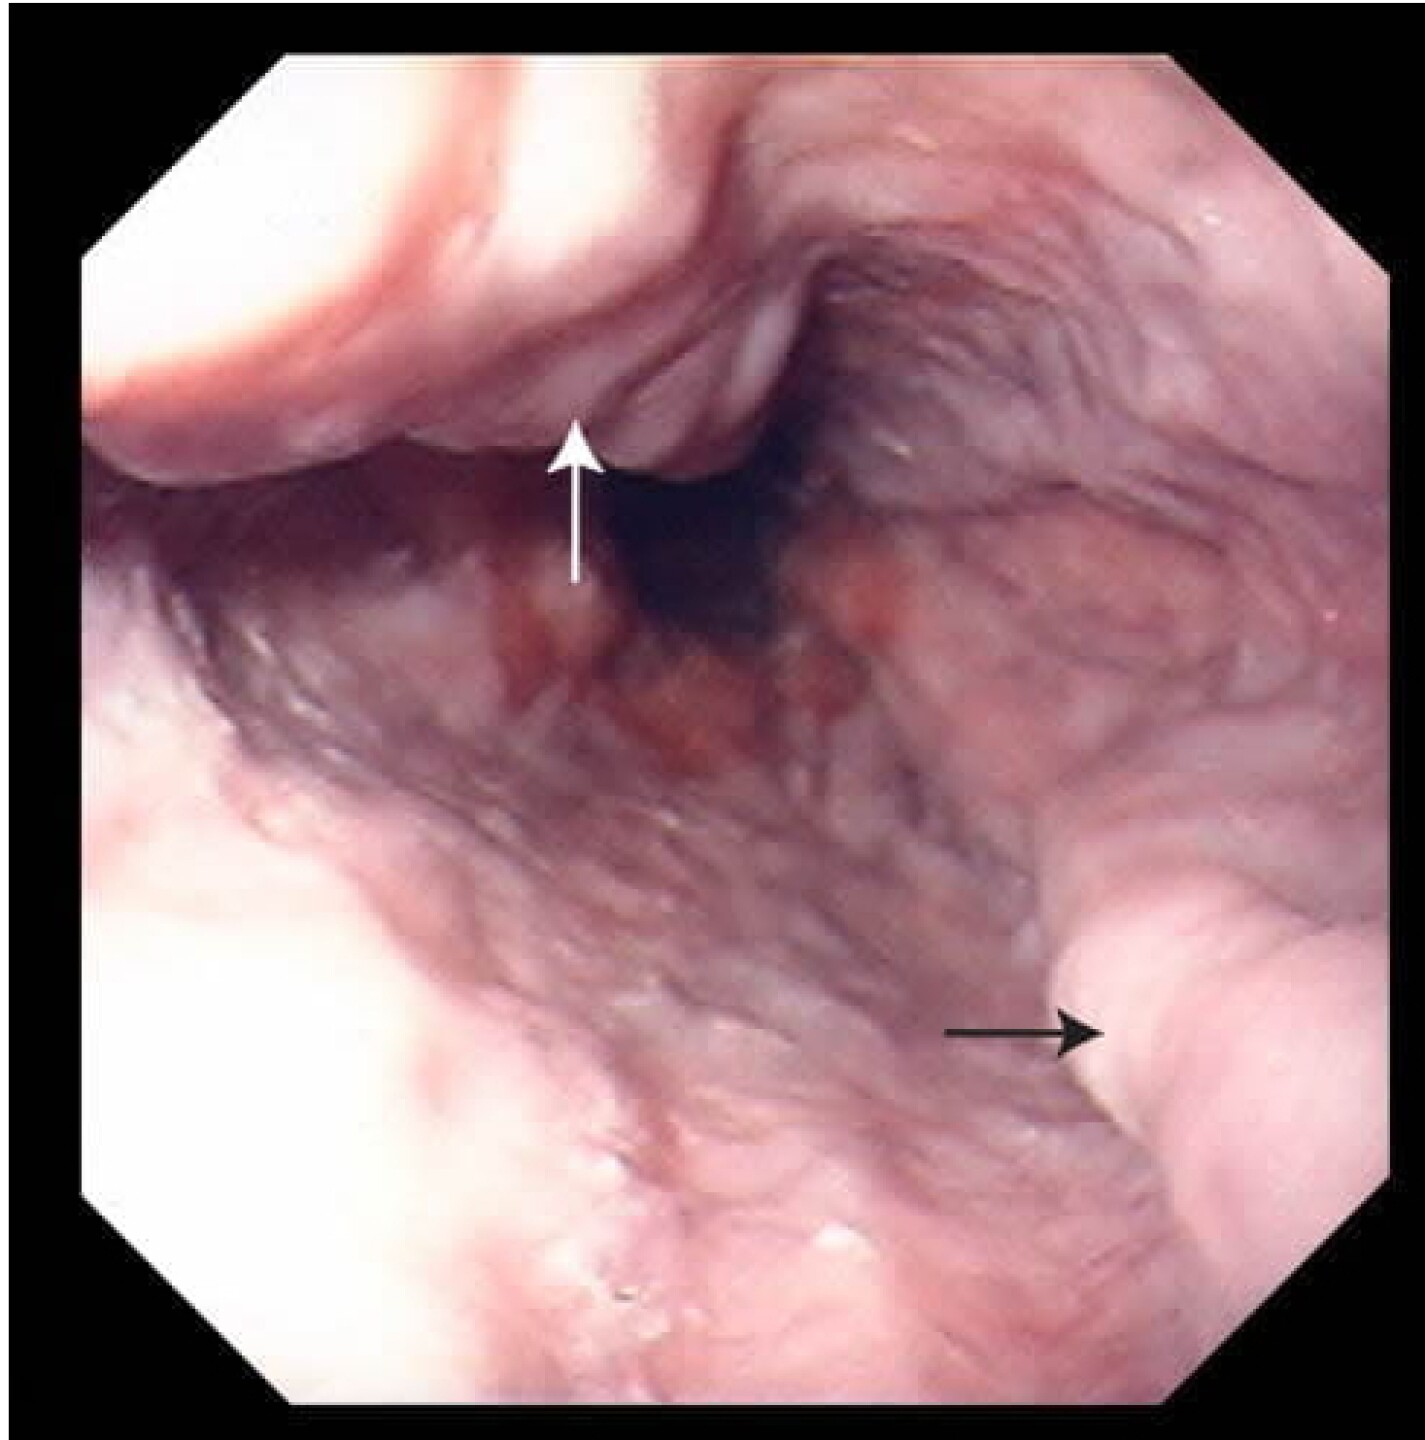

De acuerdo con varios sitios especializados en medicina, una várice esofágica es “una vena agrandada en el esófago que puede causar hemorragias graves”.

Al ser demasiado frágiles, estas “varices agrandadas” suelen romperse con demasiada facilidad y pueden causar “una hemorragia gastrointestinal masiva”, lo que provoca un shock o incluso la muerte.

Por ello, es recomendable ir con un especialista para que le hagan una endoscopia y descartar o confirmar si la causa del sangrado es realmente por este padecimiento.

Si la endoscopia muestra la existencia de una várice esofágica, el médico hará diversos procedimientos para detener el sangrado como, entre las que se puede incluir el uso de antibióticos y el cierre de la abertura con una “banda endoscópica”.